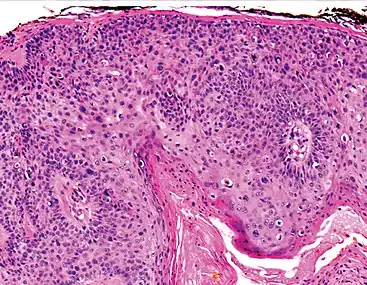

Invasive disease

In invasive cSCC, tumor cells infiltrate through the basement membrane. The infiltrate can be somewhat difficult to detect in the early stages of invasion: however, additional indicators such as full thickness epidermal atypia and the involvement of hair follicles can be used to facilitate the diagnosis. Later stages of invasion are characterized by the formation of nests of atypical tumor cells in the dermis, often with a corresponding inflammatory infiltrate.[12]